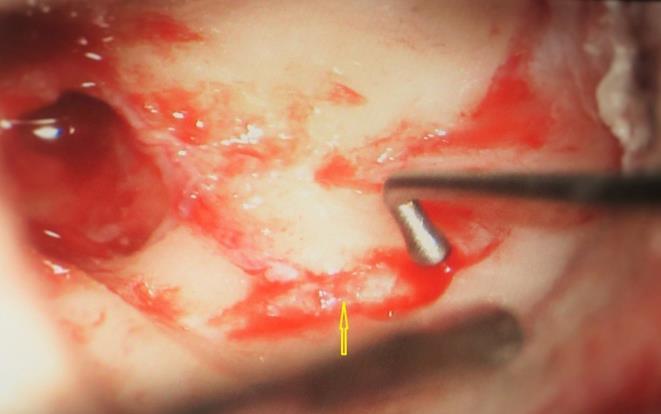

A 13 year old girl presented in ENT outpatient department with complains of recurrent right ear purulent discharge from pre and post auricular area for last 5 years. She had a history of incision and drainage in right post auricular area six months prior for similar complain. On local examination, there was right Grade II8microtia with atretic External Auditory Canal (EAC) and pre-auricular skin tag (Figure 1). A small fistulous opening was also seen in right cavum conchae region. Left ear examination was normal with intact tympanic membrane. Tuning fork tests using 256 and 512 Hz tuning forks showed moderate to severe conductive hearing loss in right ear with Rinne’s test positive in left ear. HRCT scan of temporal bones showed membranous atresia of right EAC with grade II microtia. Soft tissue density was seen filling the EAC and the entire middle ear cavity (Figure 2A). A CT based fistulogram done four months before our consultation identified multiple fistulous tracts situated in post auricular region and anterior to stylomastoid foramen in inframastoid region. These fistulous tracts were communicating through middle ear cavity (Figure 2B). There was associated erosion of posteroinferior and anteroinferior wall of EAC. Ossicles were dysplastic or eroded. Inner ear structures were normal. Patient underwent right radical mastoidectomy with wide conchal meatoplasty under general anaesthesia. Intraoperatively, there was right EAC membranous atresia with fistulous opening in cavum conchae. Cholesteatoma sac was seen filling the mastoid antrum area extending into middle ear cavity and EAC with erosion of posterior canal wall. Except remnant of malleus head which was fixed to epitympanic wall, no other ossicle was found. Oval window area showed bony depression without any overlying stapes footplate (Figure 3). Lateral semicircular canal bulge, facial nerve canal and chorda tympani were found at their usual locations (Figure 4). Obliteration of mastoid cavity posterior to vertical segment of bony facial canal was done using pedicled temporalis muscle flap to reduce the size of postoperative cavity. Middle ear cavity was covered with temporalis fascia graft.

Figure 4.Arrow pointing to exposed facial nerve (vertical segment)